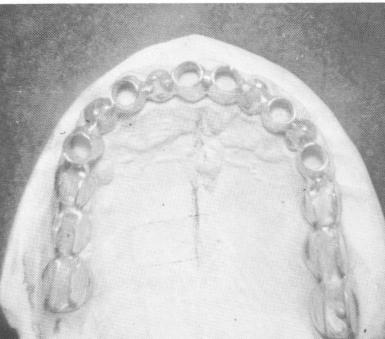

Fig. 10-253. The scalloped "tube template" with double rails on both posterior quadrants.

The tube template, designed by Linkow, is scalloped, allowing soft tissue invagination between the interproximal embrasures and providing greater surface for a frictional grip of the denture. Its buccolingual width approximates the outline of the natural teeth. Because the tubes open directly to the mucosa, it is easier to insert post type implants.

The hollow tube template was fabricated from the master cast poured from the elastic impression

taken of the edentulous maxilla (Fig. 10-253). An opposing jaw alginate (irreversible hydrocolloid) impression was also taken and, because the bite was accurate enough, the superstructure—in this case, a full arch fixed denture—was fabricated at the same time that the template was cast (Fig. 10-254). Using a denture adhesive cream on the tissue-bearing side, the template was placed into position on the soft tissue (Fig. 10-255).